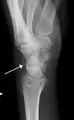

Triquetral fracture indicated by the white arrow.- Triquetral fracture as seen on lateral view of a radiograph.